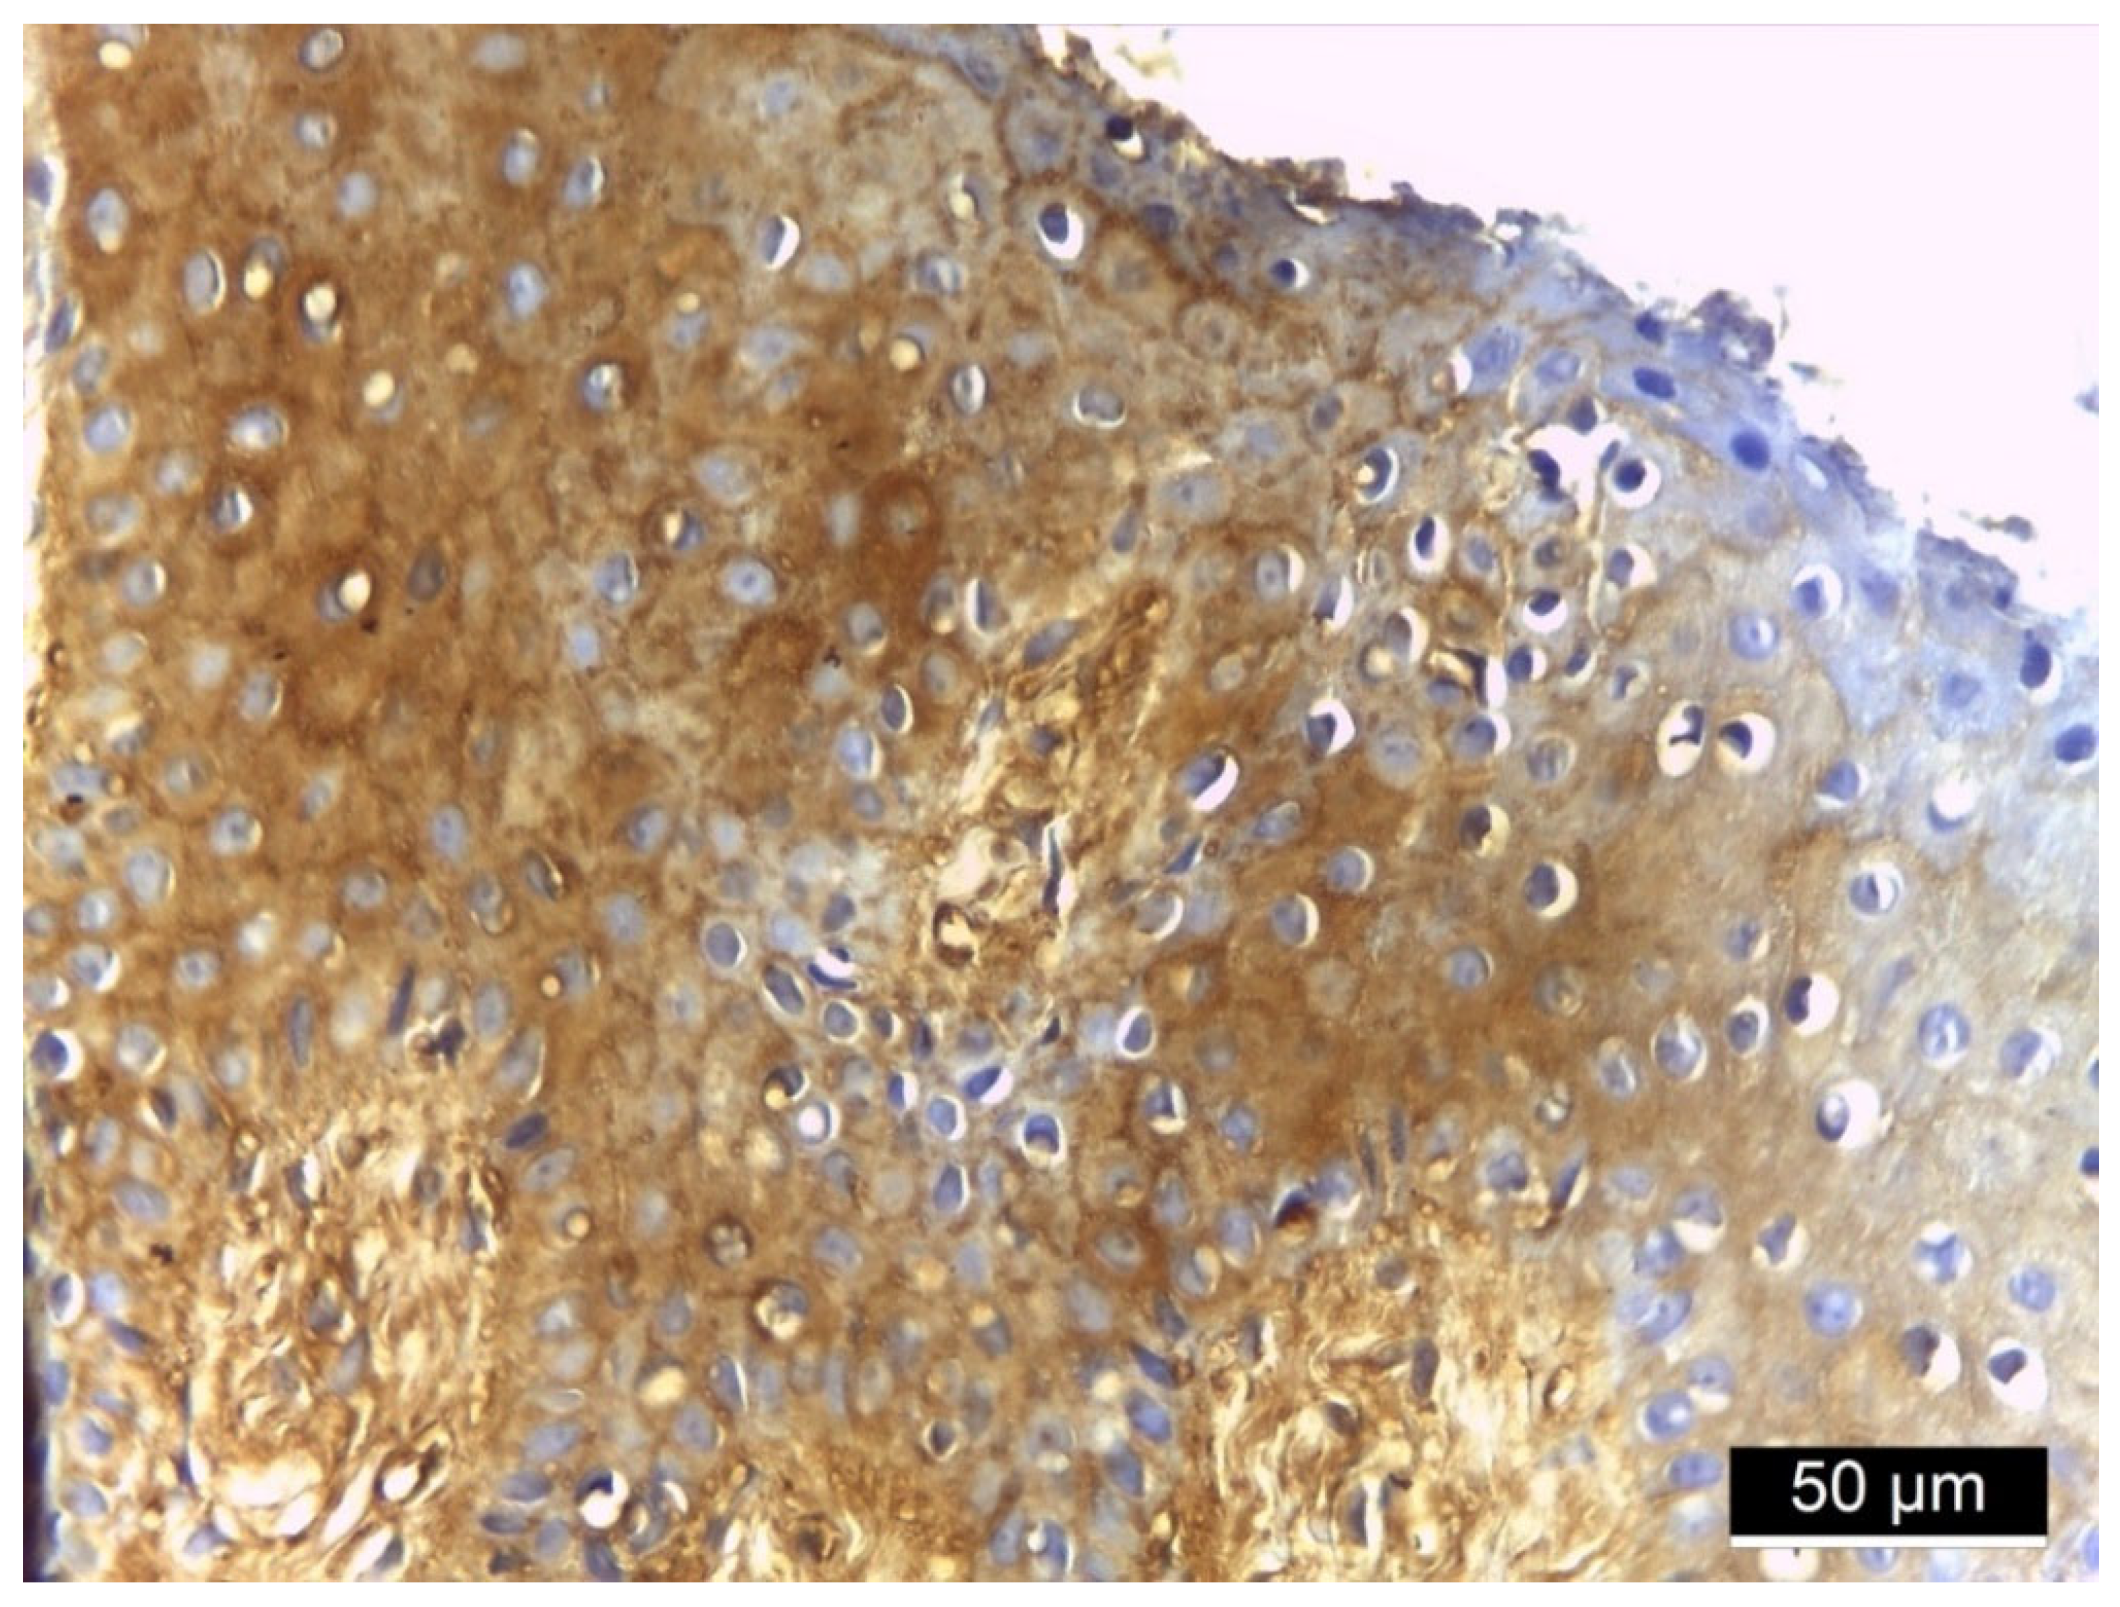

3.2. Ezrin Immunoreactivity

4.1. Ezrin Immunoreactivity